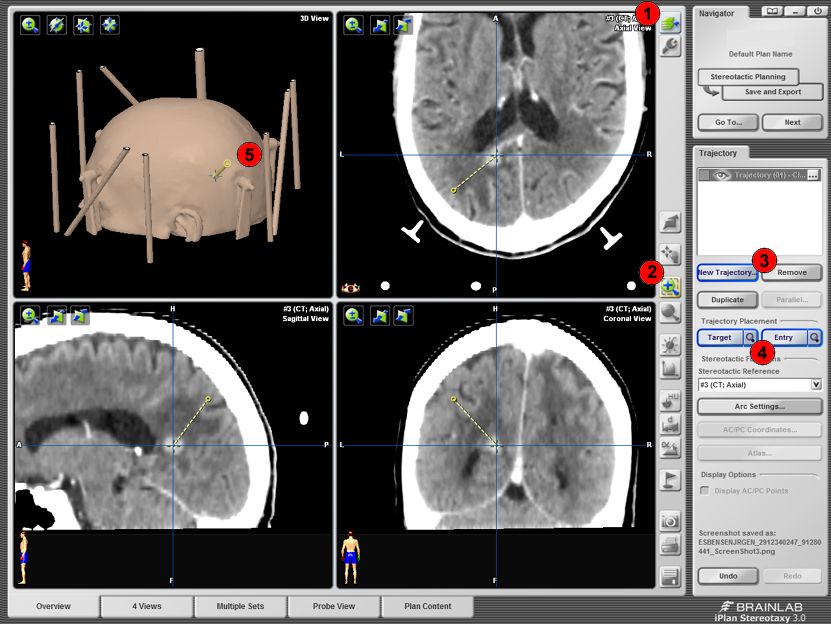

Trajectory

Man vælger scannings-serie i serie-vælgeren (1). Man zoomer ind med lup (2) og scroller i hver plan ved at rulle med musen i det pågældende vindue. Vælg New trajectory (3) og Target-knappen (4) er nedtrykket. Klik på billederne for at markere target. Tryk herefter Entery-knappen for at markere et andet punk på den linie som repræsenterer trajectory. Ved at trykke på de små forstørrelsesglas (4) kan man centrere billederne på hhv det valgte target eller enterypoint. På 3D rekonstruktionen kan man få et indtryk af hvor lokalbedøvelsen skal lægges (5).